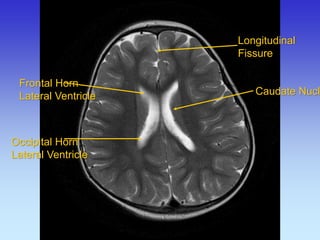

Longitudinal Fissure

Caudate Nucleus

Frontal Horn Lateral Ventricle

Occipital Horn

Lateral Ventricle